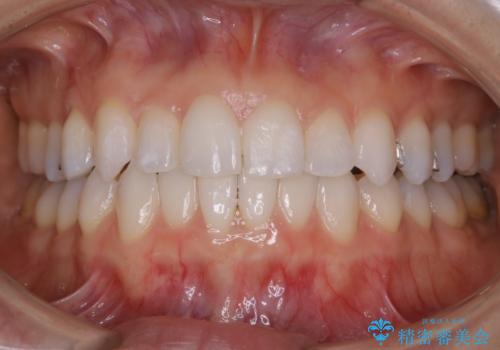

- 前歯のガタつき改善を主訴にご来院されました。

ガタつき自体は軽度で、奥歯の噛み合わせのズレもほとんどなかったため、非抜歯でマウスピース矯正装置を選択しました。

歯列の幅の拡大と歯を小さくする調整を行うことで並べるスペースの確保を行いました。この方法は、ガタつきをとりたいところに直接スペースを作ることができるので治療期間を短縮することができ効率的です。